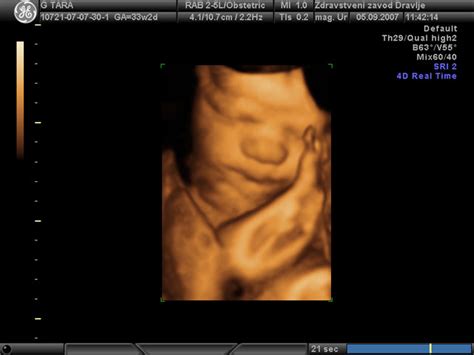

Prezgodnji porod je definiran kot porod pred dopolnjenim 37. tednom nosečnosti. V Sloveniji, kot tudi v drugih razvitih državah, se delež prezgodnjih porodov giblje okoli 6 % vseh nosečnosti. Poznamo različne kategorije prezgodnjega poroda: zelo zgodnji porodi med 24. in 32. tednom nosečnosti ter porodi med 32. in 37. tednom nosečnosti, ki jih imenujemo tudi pozni nedonošenčki. Otroci, rojeni v tem kasnejšem obdobju, so kljub primerljivim meram ob rojstvu pogosto deležni drugačne obravnave v primerjavi z donošeni otroki, čeprav so najštevilčnejša skupina prezgodaj rojenih otrok.

Razlogi za prezgodnji porod so lahko kompleksni in multifaktorski. Pogosto so povezani z vnetji plodovih ovojev ali sistemskimi okužbami pri nosečnici. Drugi dejavniki tveganja vključujejo preeklampsijo, kronično visok krvni tlak, sladkorno bolezen, bolezni vezivnih tkiv, hude nepravilnosti ploda ali hud zaostanek v rasti. Dvoplodne nosečnosti se prav tako pogosteje končajo pred predvidenim rokom. V nekaterih primerih, kljub nejasnim vzrokom, kot je bil primer v zgornjem forumu, kjer je bil izvid brisa na patogene bakterije negativen, lahko pride do prezgodnjega razpoka plodovih ovojev. V takšnih situacijah, čeprav je bil maternični vrat v 19. tednu dolg 4 cm in zaprt, je lahko vzrok za prezgodnji porod še vedno skrivnost.